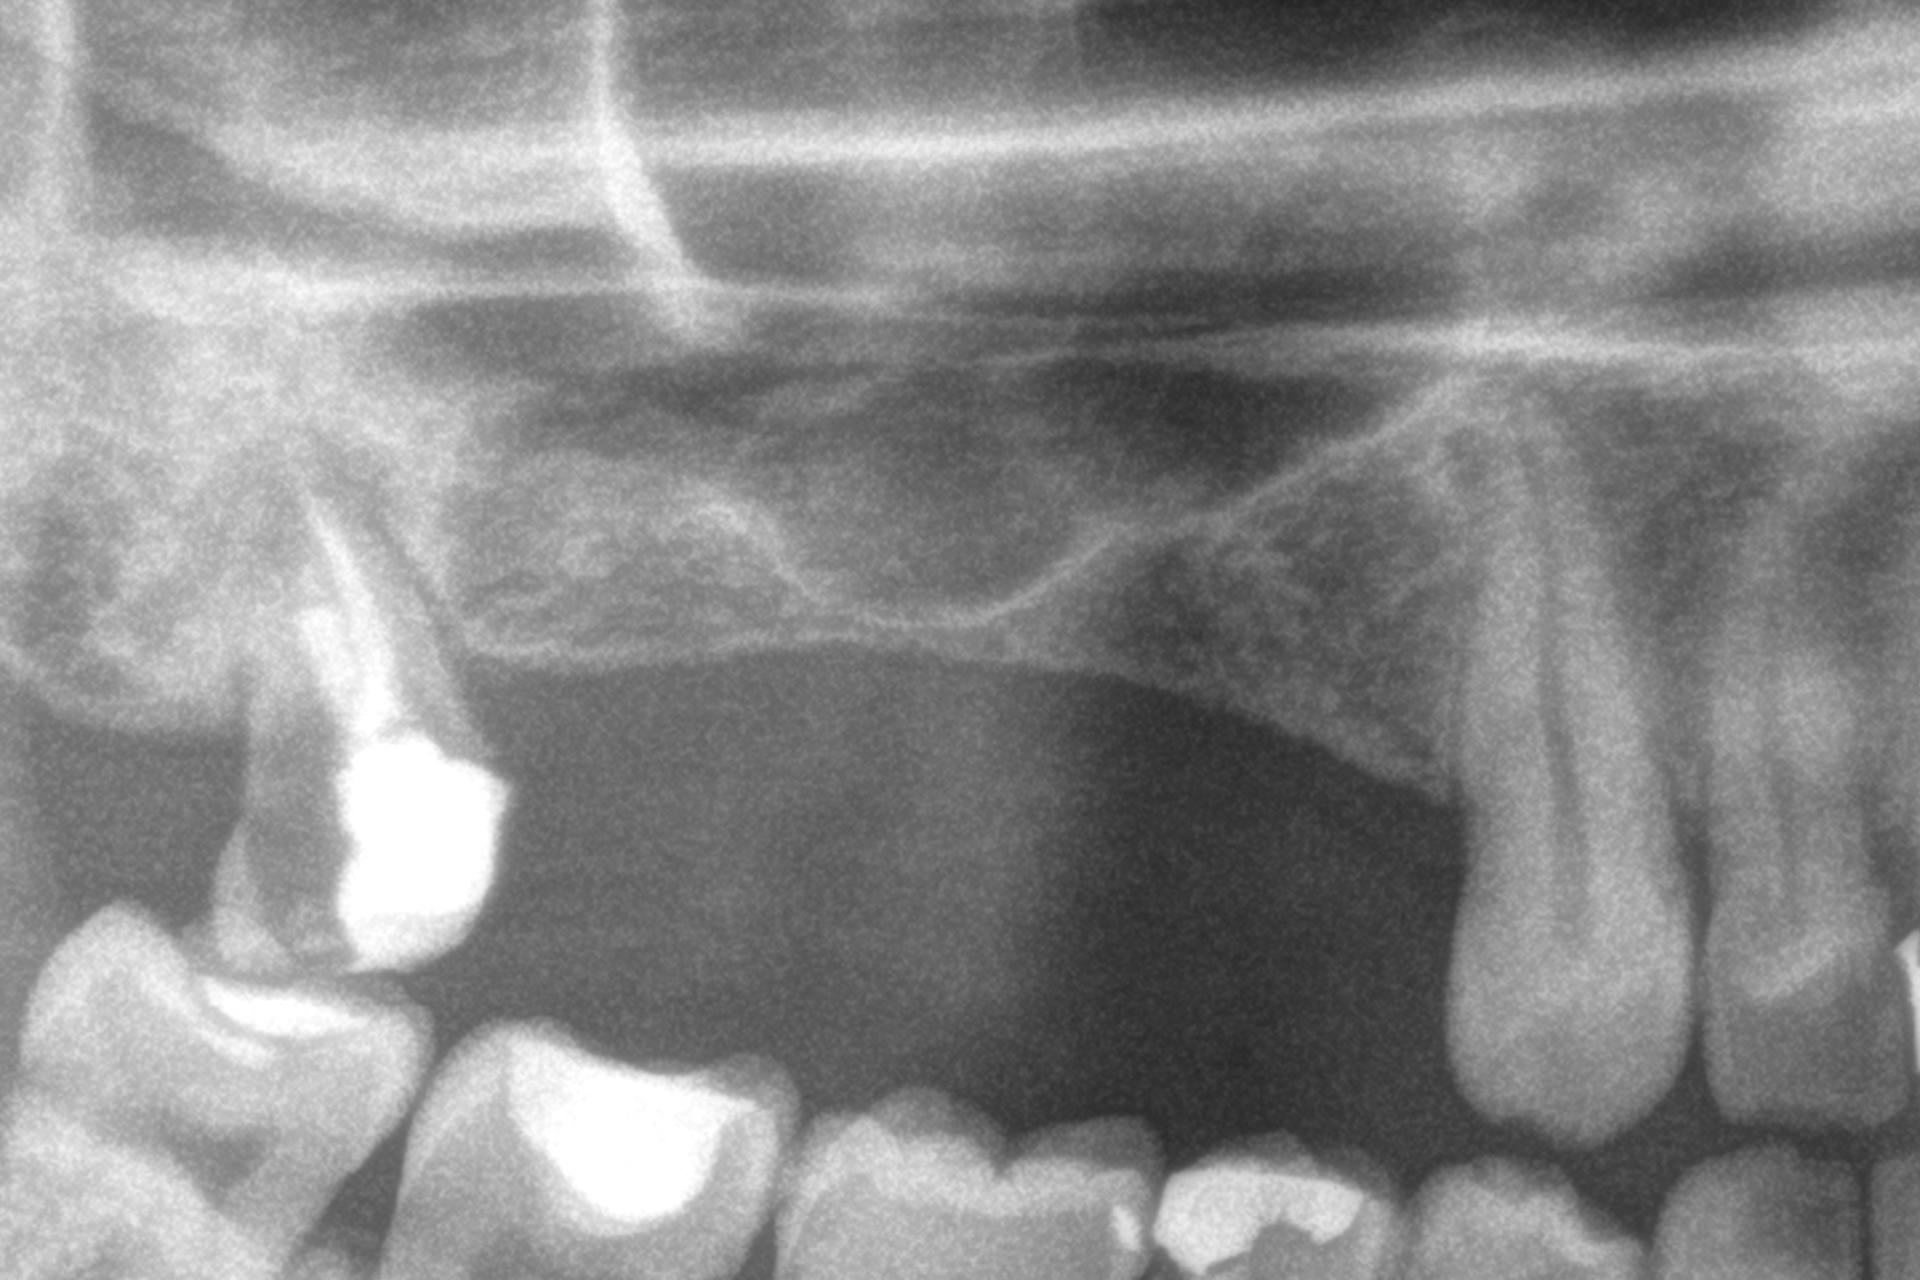

Al termine del follow-up, la perdita ossea crestale media è stata di 0,73 ± 0,18 mm in mesiale e di 0,85 ± 0,34 mm in distale. Alcuni casi clinici rappresentativi sono illustrati nelle Figure 2-10.